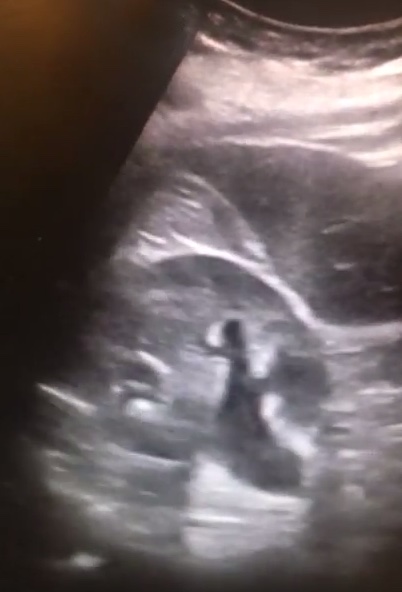

Diagnosis: Mild-moderate right hydronephrosis

- Urinary tract obstruction, in this case secondary to a distal ureteral stone, can lead to infection, sepsis, and permanent renal injury